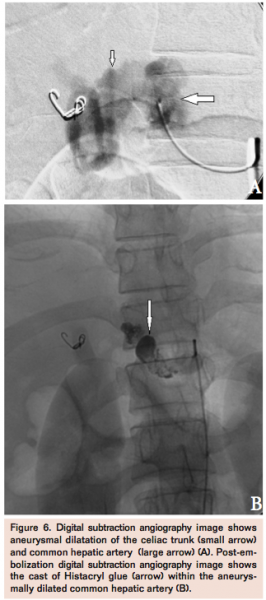

A digital subtraction angiography (DSA) was performed (Figure 3A) and the pseudoaneurysm arising from the right hepatic artery was embolized (Figure 3B) with two 0.18 coils (platinum fibered coils, Boston Scientific/Target Therapeutics) and he was discharged in a stable condition. Three days later, he presented with acute abdominal pain, pallor, and tachycardia. His hemoglobin level was 7.8 gm%. CTA revealed increased dilatation and dissection of the celiac trunk and common hepatic artery (Figure 4) associated with a right-sided perinephric hematoma. He was managed conservatively, given blood transfusions, and discharged on recovery. However, he presented 5 days later with acute abdominal pain, distension, tachycardia, and hypotension. He required intubation and inotropic supports in the intensive care unit. A repeat CT angiography showed aneurysmal dilatation of the celiac trunk and common hepatic artery and extension of the dissection associated with a large pseudoaneurysm (Figure 5). Repeat DSA was done on an emergency basis (Figure 6A) and the aneurysmally dilated common hepatic artery was embolized with 20% Histoacryl glue (Figure 6B). There was no filling of the pseudoaneurysm in the post-embolization angiogram. The patient improved and was discharged when he stabilized a few days later. He died at home a week later.